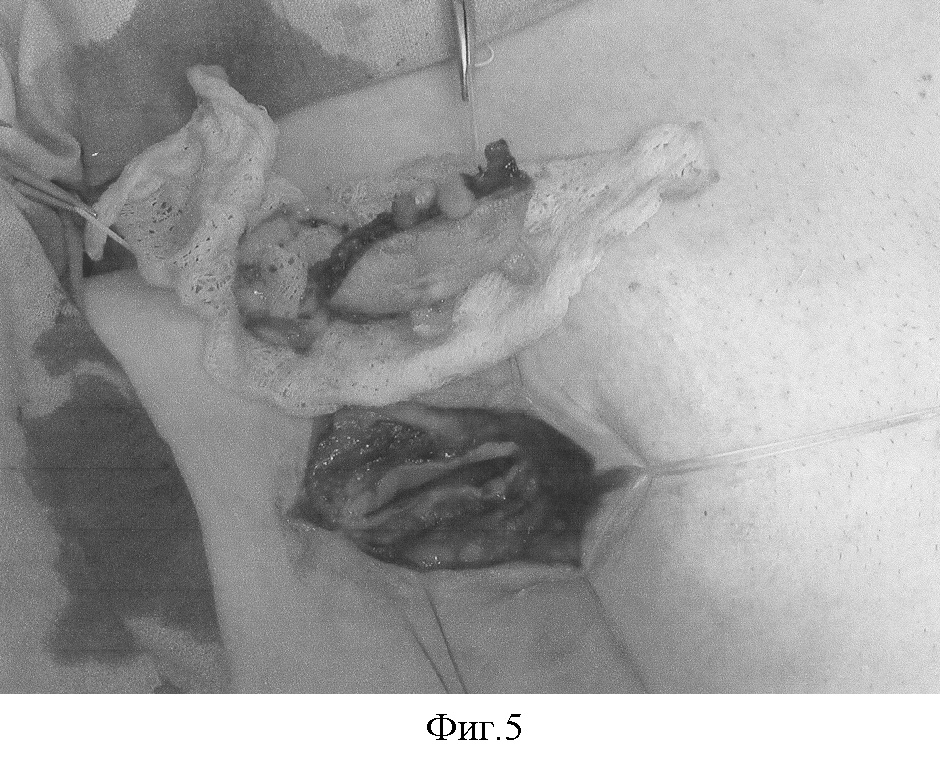

Фиг.5 – забранный единый комплекс тканей перенесен в реципиентную область.